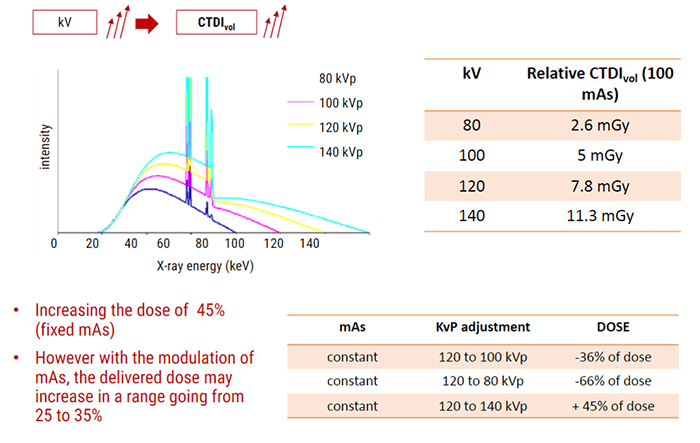

Influence of kV

Subjective Choice of the Technologist

It is important to know that X-ray penetration is an exponentially decreasing function of patient thickness. Thus, large patients will need a much larger dose. We use higher kVp to penetrate large people, large bony people, and bone. As we increase kVp, more of the beam penetrates the tissue with higher energy so they interact more by the Compton effect. This produces more scatter radiation which increases image noise, reduces contrast and increases the dose.

The type of interactions that occur between the patient’s body and the x-ray photons is a function of the selected kVp. Increasing the kVp will improve the signal-to-noise ratio. But decreasing the kVp will reduce the patient dose especially in pediatric and small adults. For contrast resolution of the gray-white matter (or soft tissue) in the brain, the high technique is necessary. Imaging in large patients can be improved also by using the maximum kVp along with an increase in scan time.

Lets now look at mAs and its effect on the dose.

Influence of mAs

CTDIvol is directly proportional to the tube Current and acquisition time. mAs also affects patient dosage. It determines the total number of electrons and only the quantity of the photons is affected by a change in mAs. When mAs is selected, remember that longer scan times will require longer tube cooling and can cause an increase in patient motion. But an increase in scan rotation time will result in better resolution.

The increase of mA and kVp will improve the signal-to-noise ratio but also increase the dose to the patient. Remember, doubling the mAs will increase the CTDIvol.